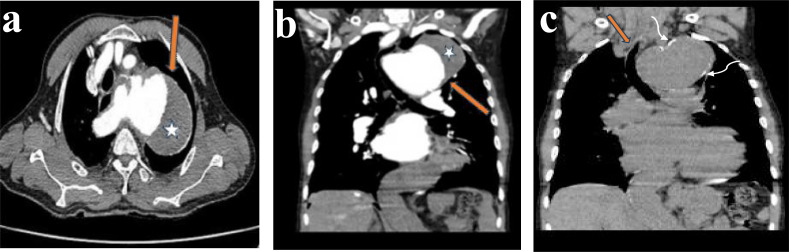

Background: Thoracic aortic aneurysm is an increasingly recognized condition that is sometimes diagnosed incidentally on imaging examinations performed to evaluate other unrelated conditions. Symptomatic presentations of thoracic aortic aneurysms may be due to mass effect on the airway, esophagus, recurrent laryngeal nerve and the thoracic spine. Alternatively, they may present with the dreaded complication of aortic dissection or rupture.Occasionally abnormalities of the aortic contour or size can be detected on routine chest x-ray. However, it is difficult to confidently diagnose thoracic aortic aneurysm on chest x-rays as mediastinal masses may mimic aortic aneurysms. Computed tomography (CT) or magnetic resonance (MR) aortography, with the advantage of obtaining 3D volumetric data, remains the gold standard of imaging with sensitivity and specificity approaching 100%.

Method: This is a case report of a 58-year-old man with breathlessness and features of congestive cardiac failure. Preliminary chest X-ray revealed a huge soft tissue opacity in the left upper zone of the lung which was conformed as aneurysmal dilatation of the thoracic aorta on chest computed tomography.